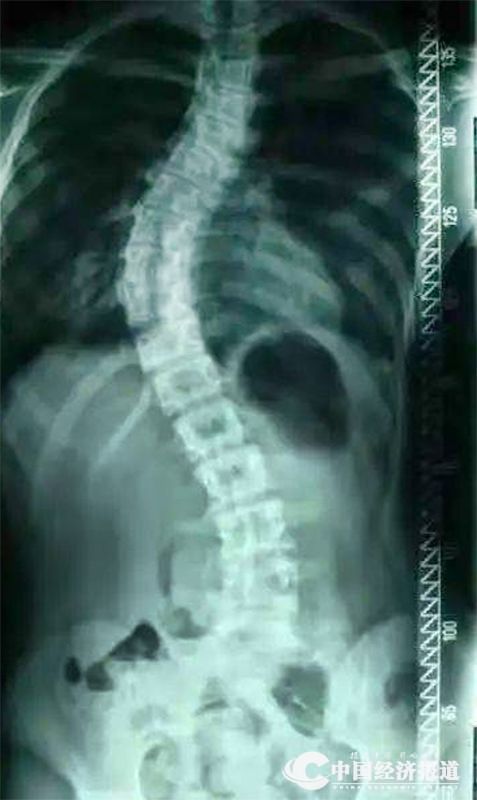

国家儿童青少年脊柱侧弯防控工作组组长、北京大学人民医院脊柱外科主任刘海鹰表示,脊柱侧弯是脊柱偏离正常的中线产生的一个畸形,它实际上是还伴随着脊柱的旋转,跟拧麻花似的,它是一个旋转,还有一个就是侧面的后突,整个来说的话,才叫脊柱侧弯。专家表示,脊柱侧弯病因较多,最常见的有先天性脊柱侧弯、特发性脊柱侧弯,以及神经肌肉性脊柱侧弯等。

(图片来源:中国妇女报)

李捃铭表示,凡是脊柱有大于等于10°的侧方弯曲即为脊柱侧弯,应尽早治疗,否则情况糟糕的话就要进行手术了。那么如果对脊柱侧弯放任不管,会带来哪些严重后果呢?

脊柱侧弯,不仅会影响患者的形体美观,还会造成肌肉紧张,导致背痛发生。而当脊柱侧弯严重到一定程度时,还会造成神经损害,压迫肺部,甚至会出现影响呼吸的症状。中年以后的话,脊柱和其他器官也一样,都在发生老化,有的就是产生的一种成人性的退变性的脊柱侧弯,脊柱的变形、增生,会造成椎管的狭窄,进而产生腰疼和下肢的这些症状。